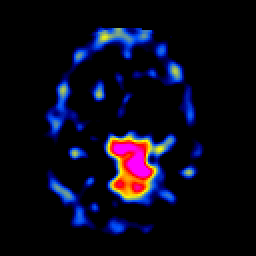

SPECT TL Study #5 -- Slice #37

[Home][Help][Clinical][Tour 1][Tour 2][Tour 3] Slice 37